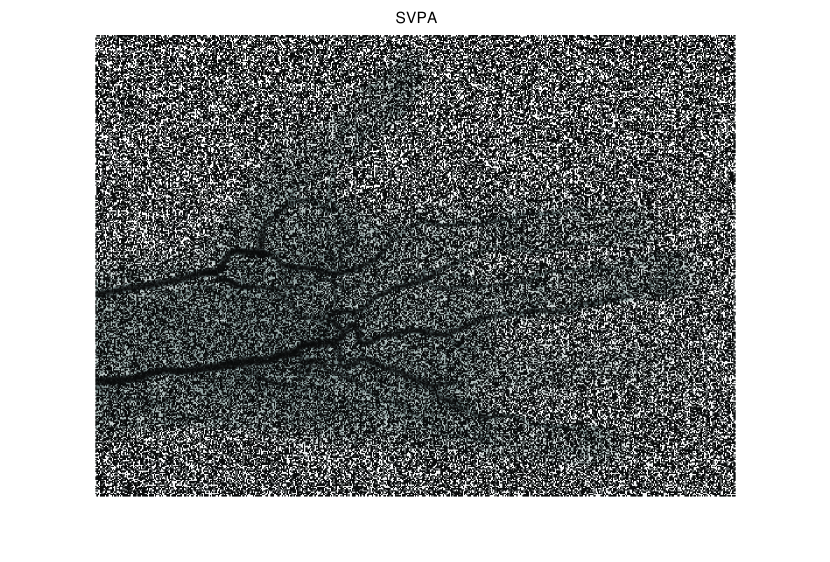

In this section, we first present numerical results of ISVTA for matrix completion problems, and then compare it with some state-of-art methods (singular value thresholding algorithm (SVTA) and singular value projection algorithm (SVPA) respectively proposed in [11] and [31]) for image inpainting problems. Numerical experiments on matrix completion problems show that our method performs powerful in finding a low-rank matrix and the numerical experiments about image inpainting problems show that our algorithm has better performances than SVTA and SVPA. Among all of the experiments, differing from the Scheme 2, we set , and

5.2 Image inpainting

In this subsection, we demonstrate performances of ISVTA on image inpainting problems. The ISVTA is tested on some medical grace images ( Brain angiography image (BAI), Hand angiography image (HAI) and Intracranial venous image (IVI)). We use the SVD to obtain their approximated low-rank images with rank , respectively. Numerical results of ISVTA for theses low-rank image inpainting problems are reported in Table 5, 6, 7, 8.

Table 5, 6 show that ISVTA performs powerful in finding a low-rank matrix on image inpainting problems. Indeed, we could get an exact low-rank image by the ISVTA by choosing proper . Moreover, it is necessary to point out that our method does not work well for all , and we can find that is not a good strategy for the low-rank IVI either or . The numerical results of ISVT, SVTA and SVPA compared in Table 5, 6, 7, 8, 9, 10 under same circumstance show that the ISVT algorithm performs far more better than ISTA and SVPA on image inpainting problems for some proper .